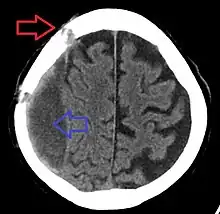

| Subdural hematoma as marked by the arrow with significant midline shift | |